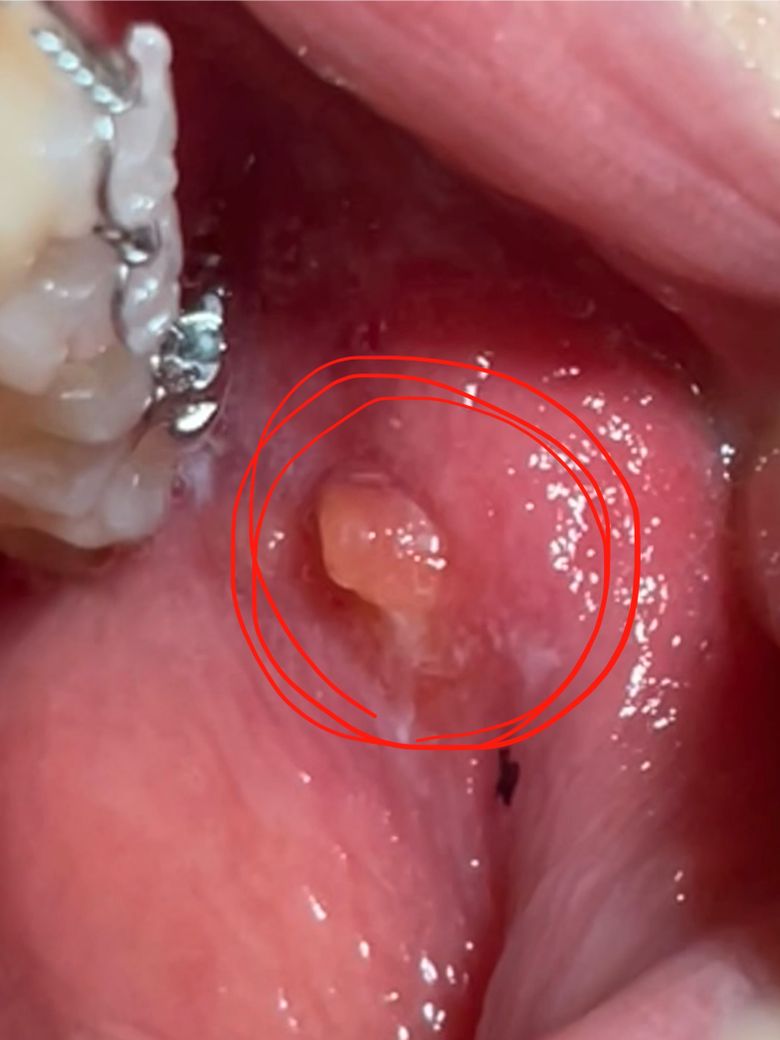

치과의사 선생님들 도와주세요! 치아교정 후 볼에 뭐가 튀어나왔습니다

치아교정을 하고 다음날 보니 사진처럼 철사 닿는 곳 볼에 뭐가 튀어나왔습니다. 만지면 좀 아프고요. 짜면 없어질 줄 알고 짰더니 옆에 피만 나고 그대로입니다.

그대로 두면 사라질까요..? ㅠㅠ 무슨 약이라도 발라야 하나요.. 치과의사 선생님들 왜 그런 건지 제발 알려주세요. 부탁드립니다

교정장치에 자극을 받아 생긴 것입니다. 그냥두면 없어집니다. 교정장치에 껌 같이 붙히는 것이 있으니 치과에 가서 달라고 해서 붙히면 자극이 덜 갑니다.

볼에 교정기 등이 자극을 주면서 생긴 것으로 예상되며 억지로 짜지 마시고 치과에 가보시는 게 좋습니다.

교정장치에 볼살이 계속 자극을 받으면서 물집이 생긴거 같습니다. 큰 문제가 잇는건 아니고 터트리시면될것같습니다.

볼살이 자극을 받아 생긴 섬유종의 일종으로 보입니다. 치과 가서 처치 받으시기 바랍니다. 보통은 악성이 아니라면 절제합니다.